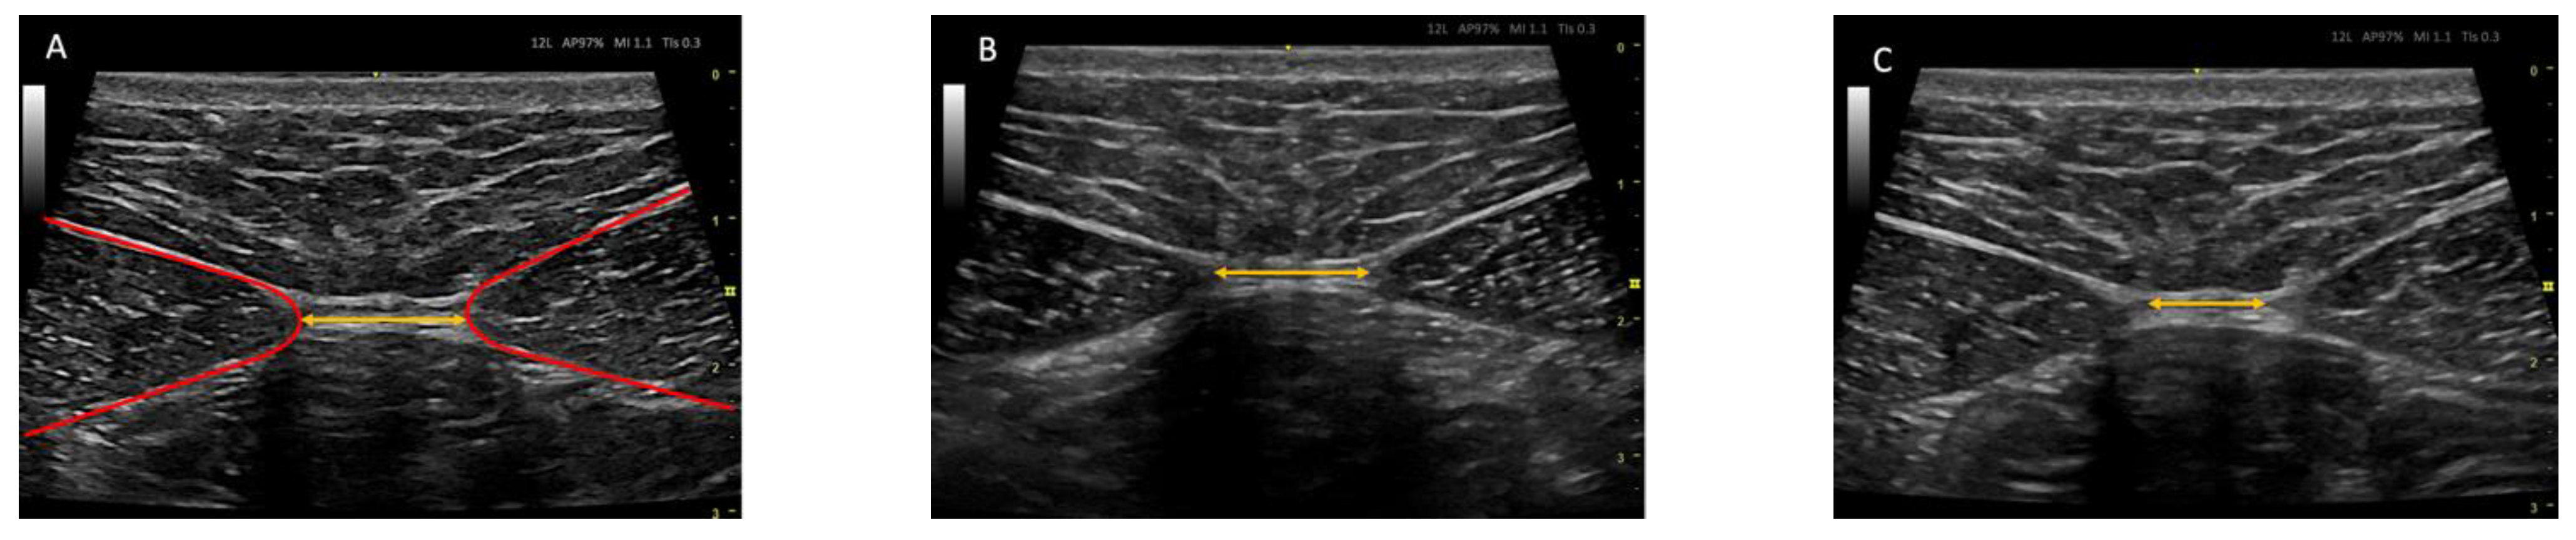

2.7. Ultrasound Protocol

2.8. Outcome Measurements/Descriptive Data